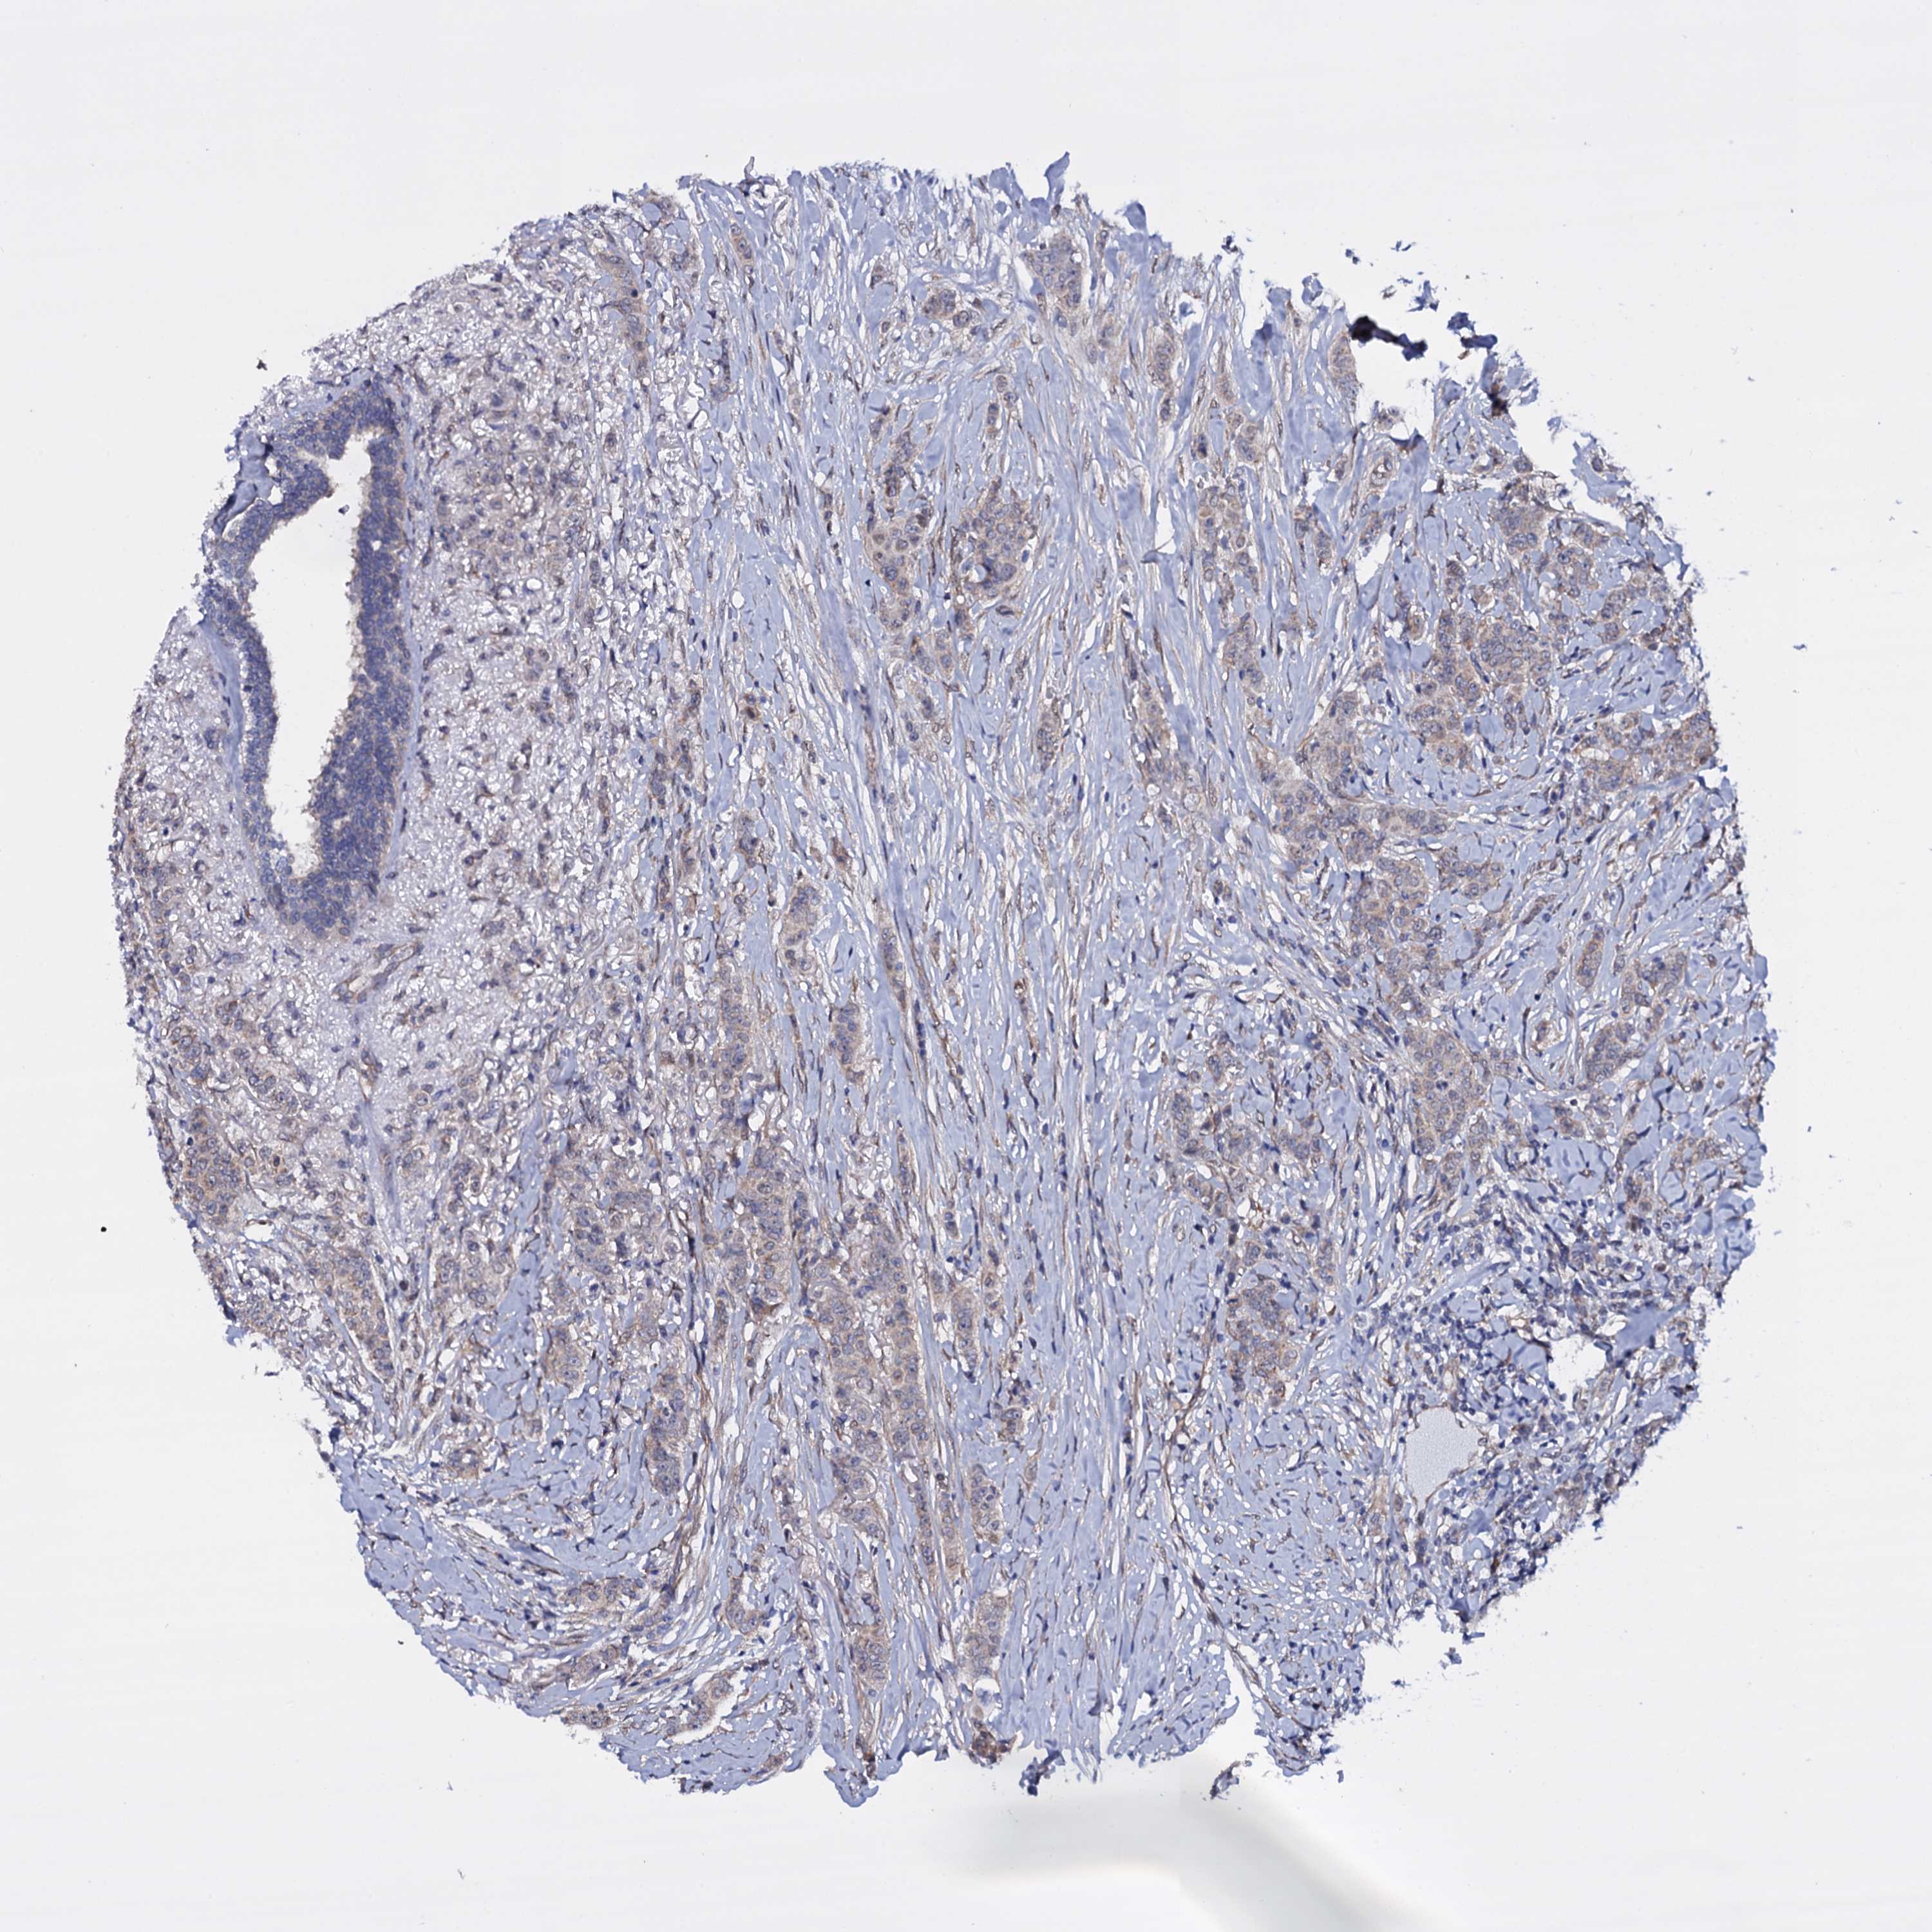

CANCER BREAST CANCER Show tissue menu

BRCA TCGA BRCA VALIDATION PROTEIN EXPRESSION